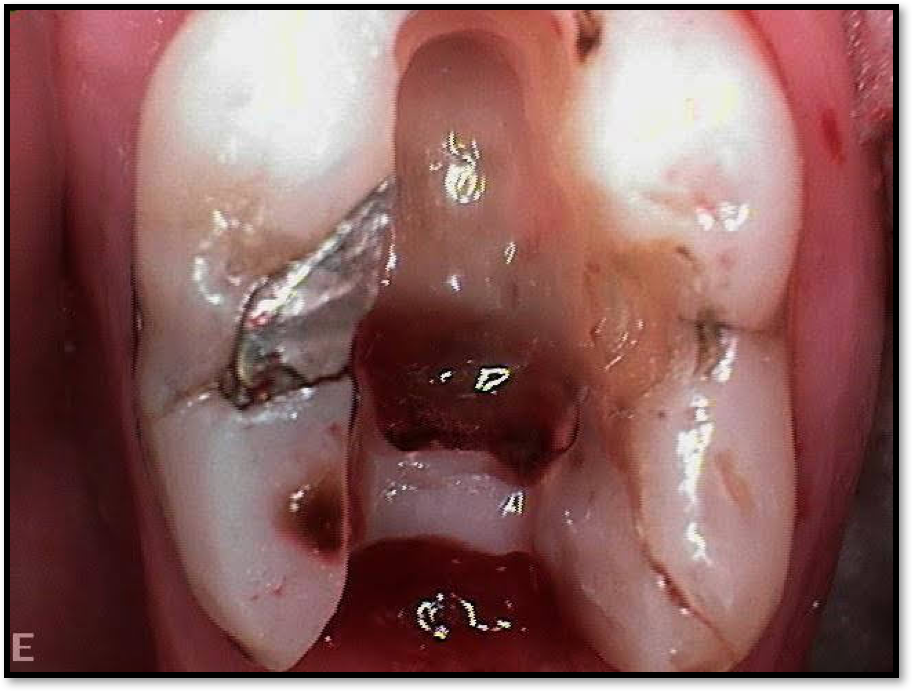

In deciding whether to use a post, the clinician must take the unique factors involved in each case into consideration. Figure 18 shows a case where the post was essentially useless and not congruent with the walls of the tooth. Figure 19 shows what the tooth looked like without the post. There was some decay, but the clinician was still able to save the tooth. Figure 20 shows the postoperative radiograph; Figure 21 was taken 6 months later. The clinician had told the patient that healing would need to be checked 6 months postoperatively to determine whether she could get a crown. There were two options for the tooth: (1) doing what the clinician did, which was to build internally as well as from mid-root with composite, or (2) use a fiber post. Several fiber posts could have been placed in the tooth as a better option, but this patient did not want to spend much and was unsure about the crown.

Fig 18. A case where the post was essentially useless and not congruent with the walls of the tooth.

Figure 18

Fig 19. The tooth without the post.

Figure 19